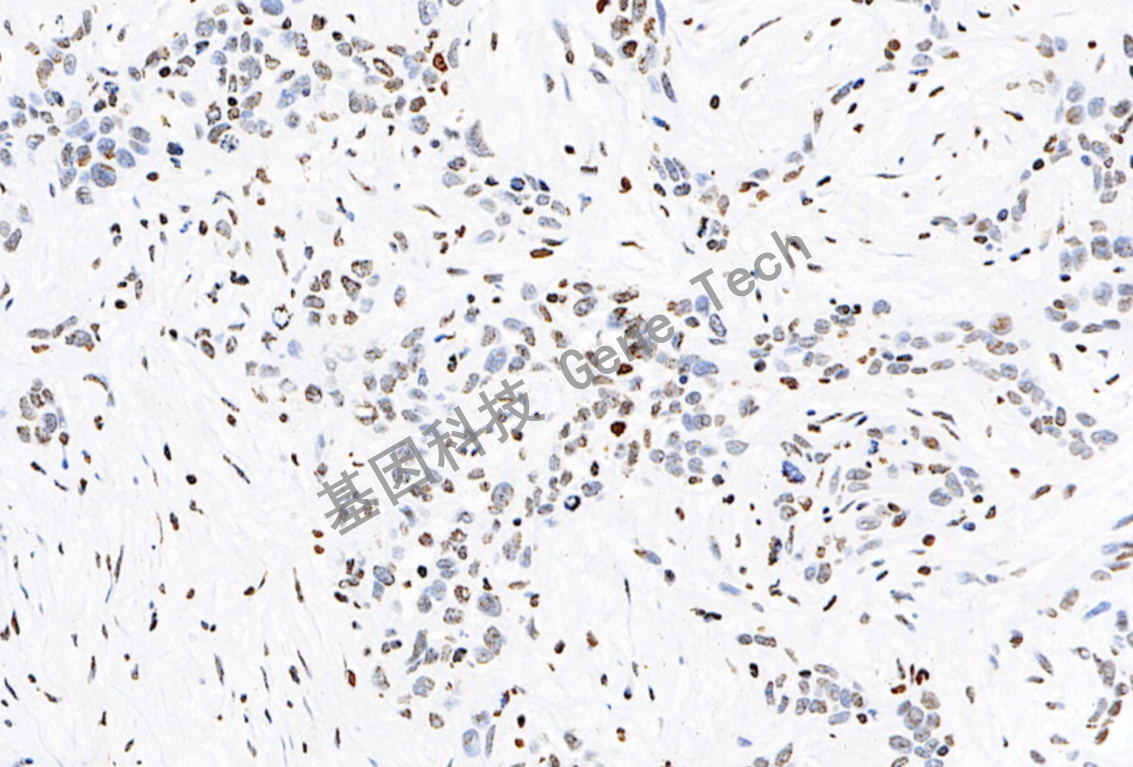

肺腺石蜡切片,用 ERCC1(GT2155)染,细胞核阳性,DAB 显色。

肺癌石蜡切片,用 ERCC1(GT2155)染,细胞核阳性,DAB 显色。